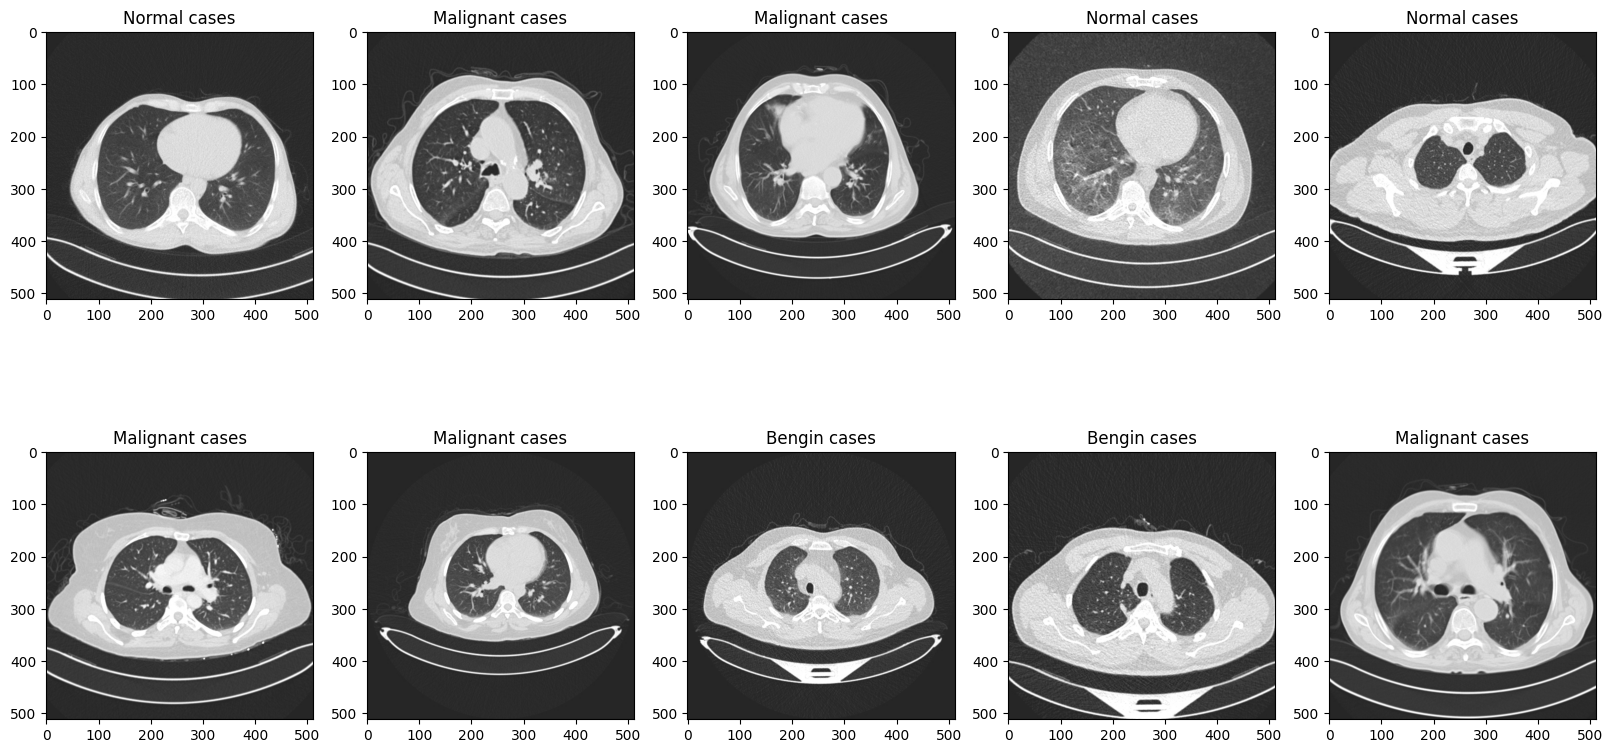

plt.figure(figsize=(20, 10))

for i in range(10):

test_img_path = os.path.join(test_root, test_file_list[i])

ori_img = Image.open(test_img_path).convert('RGB')

plt.subplot(2, 5, (i+1))

plt.title(test_file_list[i].split('/')[-2])

plt.imshow(ori_img)

plt.show()